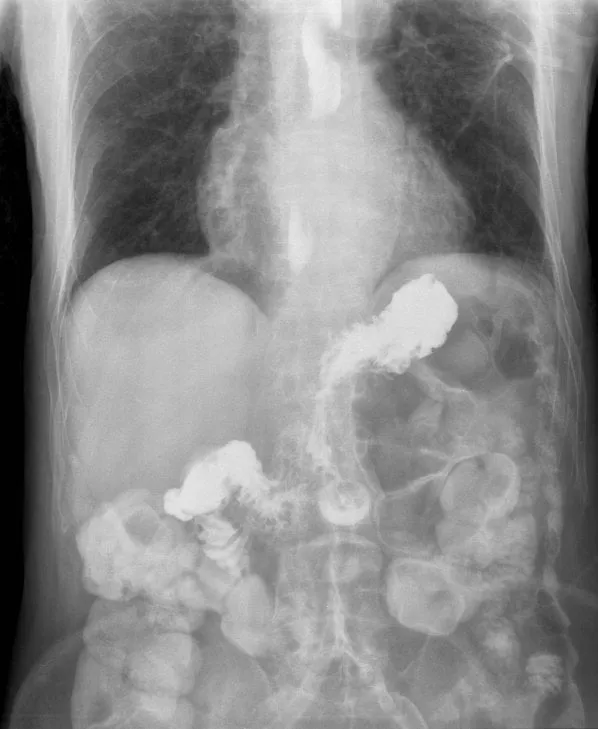

Photo : radiographie montrant un agent de contraste radiologique injecté dans l'estomac et remontant dans l'œsophage avec le reflux